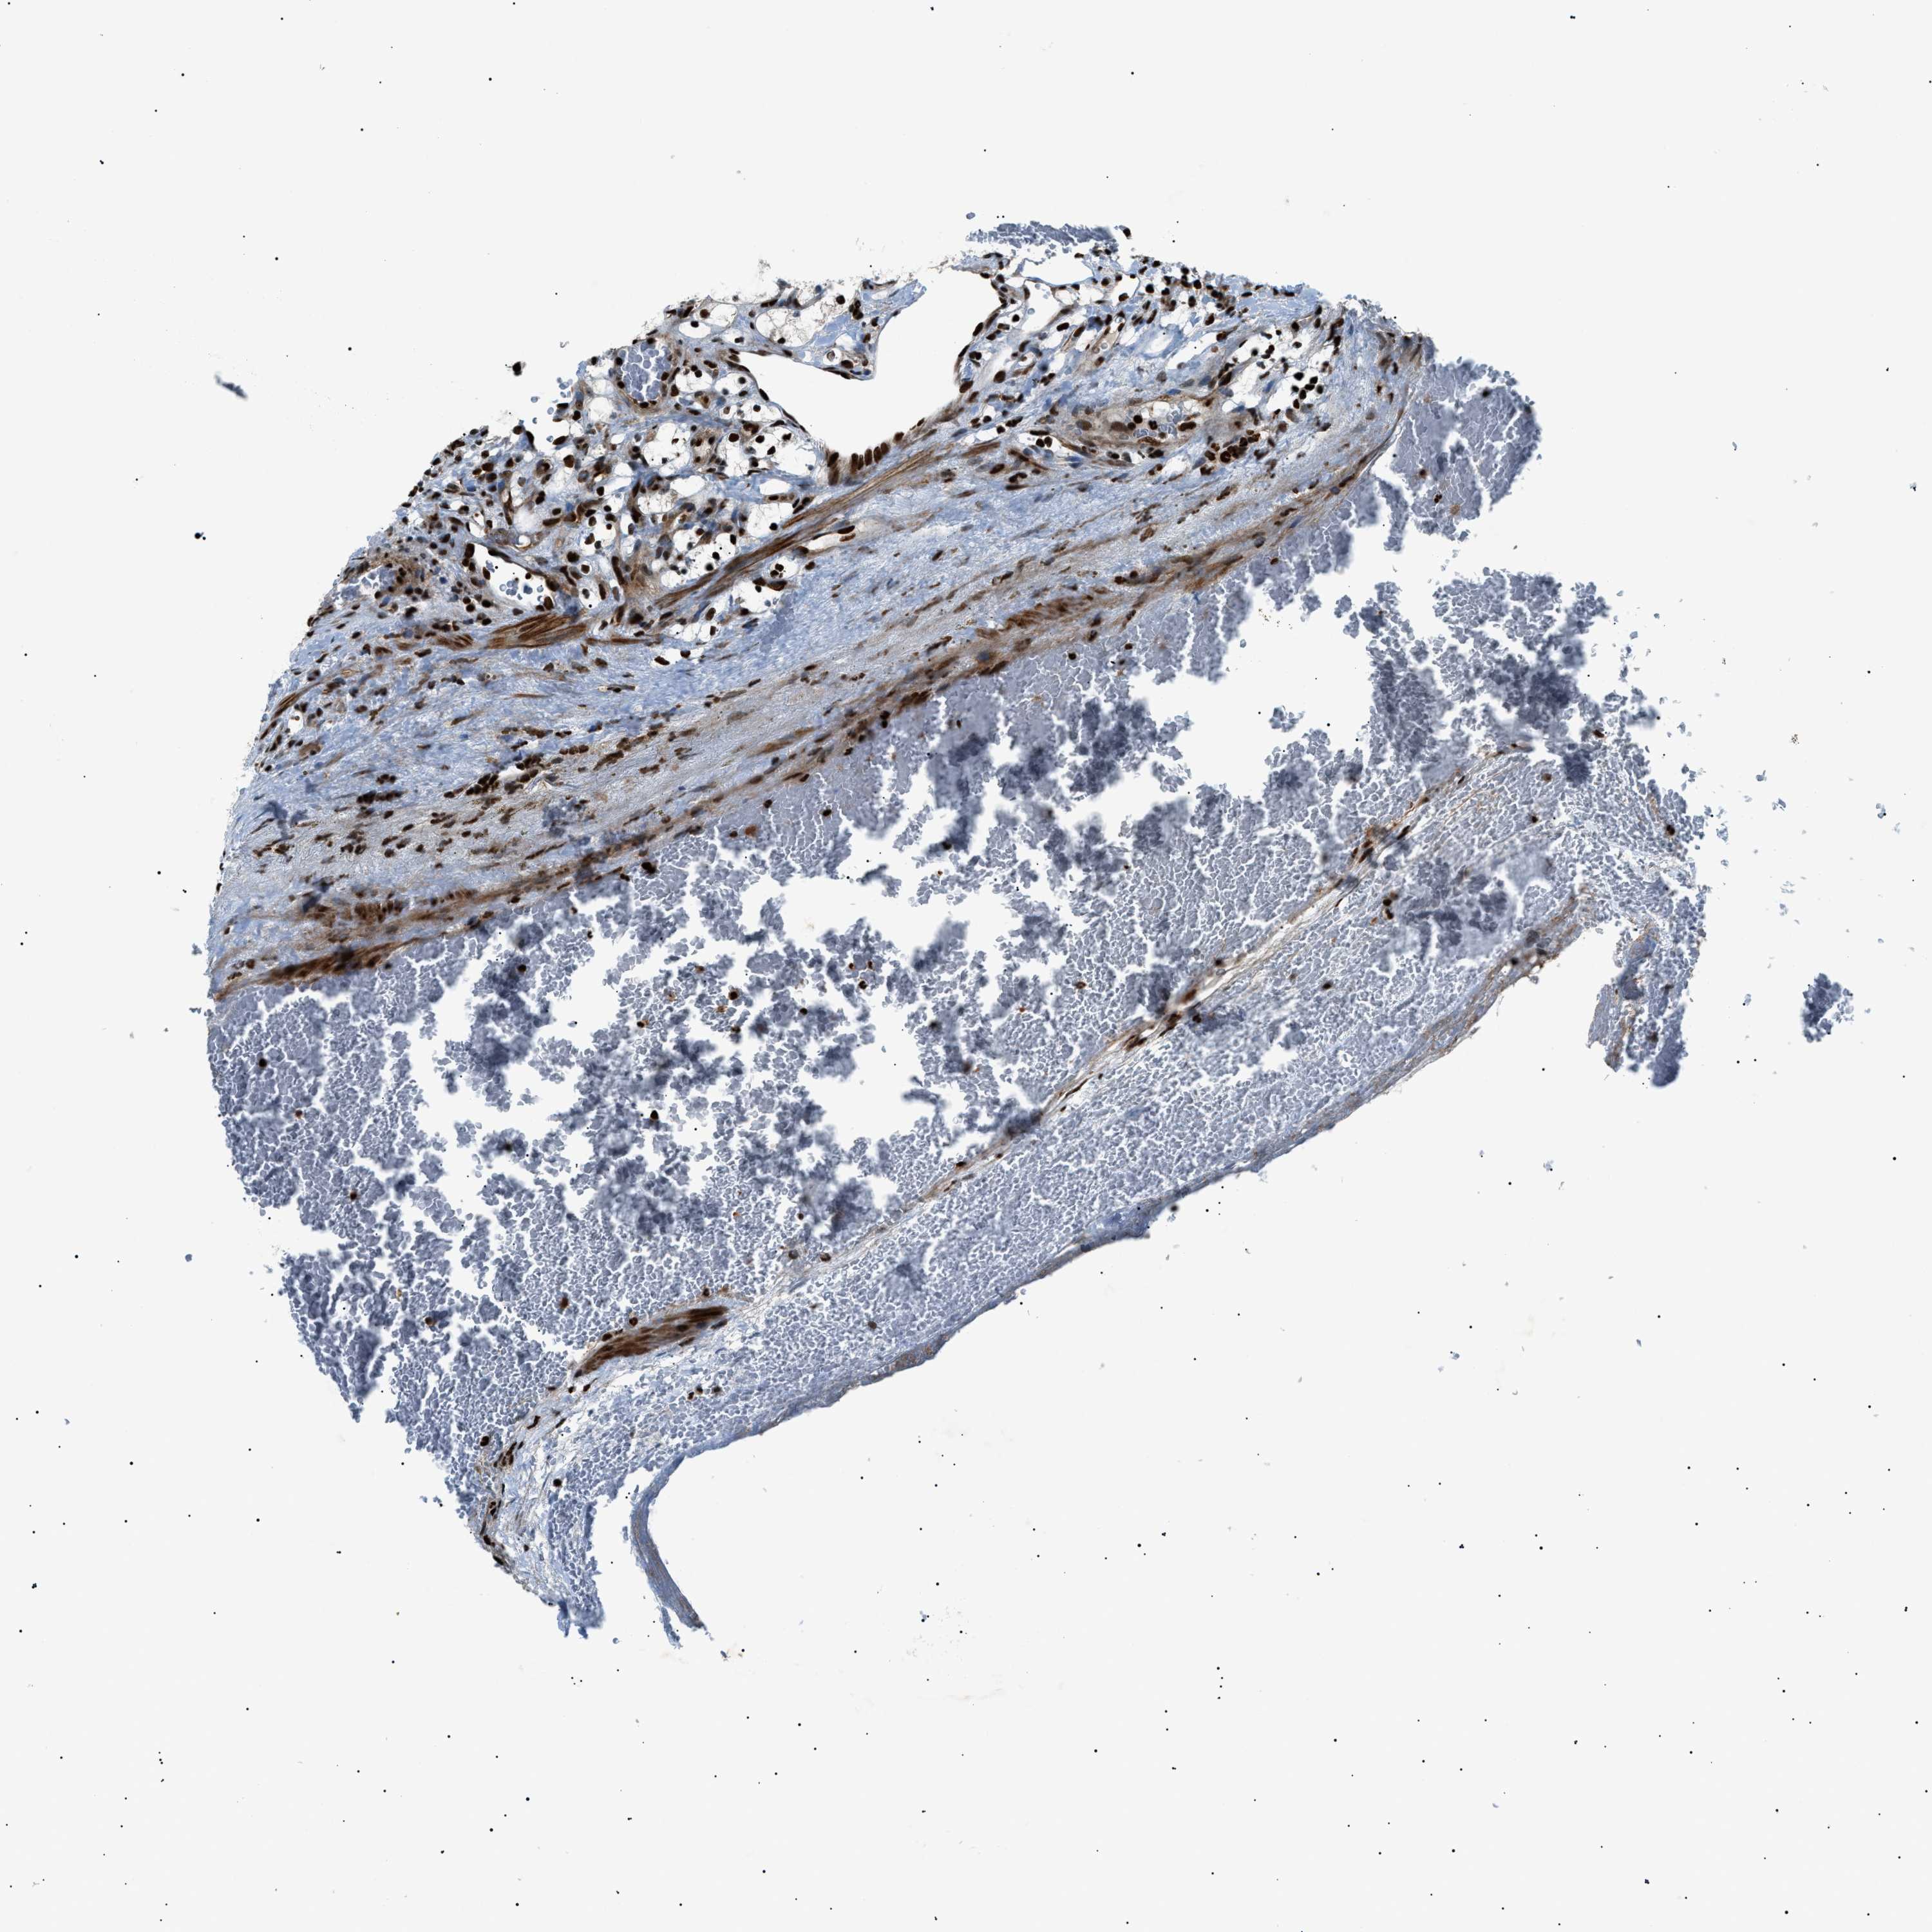

KIDNEY RENAL CLEAR CELL CARCINOMA (VALIDATION) - Interactive survival scatter ploti

The Survival Scatter plot shows the clinical status (i.e. dead or alive) for all individuals in the patient cohort, based on the same data that underlies the corresponding Kaplan-Meier plots. Patients that are alive at last time for follow-up are shown in blue and patients who have died during the study are shown in red.

The x-axis shows the expression levels (FPKM) of the investigated gene in the tumor tissue at the time of diagnosis. The y-axis shows the follow-up time after diagnosis (years). Both axes are complimented with kernel density curves demonstrating the data density over the axes. The top density plot shows the expression levels (FPKM) distribution among dead (red) and alive patients (blue). The right density plot shows the data density of the survived years of dead patients with high and low expression levels respectively, stratified using the cutoff indicated by the vertical dashed line through the Survival Scatter plot. This cutoff is automatically defined based on the FPKM cutoff that minimizes the p-score. The cutoff can be changed by dragging the vertical line or by entering a cutoff value in the square labeled "Current cut-off".

Under the Survival Scatter plot the p-score landscape (black curve; left axis) is shown together with dead median separation (red curve; right axis). Dead median separation is the difference in median mRNA expression between patients who have died with high and low expression, respectively. It is calculated as follows: median FPKM expression of dead patients with high expression - median FPKM expression of dead patients with low expression. This is intended to aid the user in visually exploring custom cutoffs and the associated p-scores and dead median separation.

Individual patient data is displayed and can be filtered by clicking on one or more of the category buttons on the top of the page. Categories describing expression level and patient information include: high, low, alive, dead, female, male and tumor stages. The scale of the x-axis can be toggled between linear and log-scale by clicking on the "x log" button. Mouse-over function shows TCGA ID, patient information and mRNA expression (FPKM) for each patient.

& Survival analysisi

Kaplan-Meier plots summarize results from analysis of correlation between mRNA expression level and patient survival. Patients were divided based on level of expression into one of the two groups "low" (under cut off) or "high" (over cut off). X-axis shows time for survival (years) and y-axis shows the probability of survival, where 1.0 corresponds to 100 percent.

PRKX is not prognostic in Kidney Renal Clear Cell Carcinoma (validation)

Best expression cut offi

: 8.82

Average pTPM 11.5

Number of samples 100